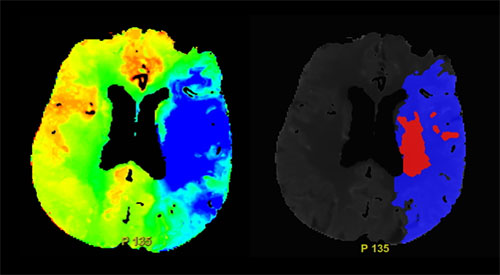

図3) MTT(左)とペナンブラ領域(右)

同社ワークステーションであるAdvantage WorkstationではCTP撮影終了後数分で画像解析が完了し、診断を行う事が可能である。CTP解析画像はカラーマップの色調から定量的に灌流異常域を評価することや、虚血コアとペナンブラ領域の解析画像も作成できる(図3)。また、CTP画像を用いてサブトラクション処理を行った4D画像を作成することができ、血流動態や側副血行路の評価にも有用である。 急性期脳梗塞の診断では、脳梗塞の評価だけでなく血管の解離・狭窄や、アンギオアクセスルートの評価も同時に求められている。そこで当院では、これらの要望に対応できる新たな撮影プロトコルを以下のように考案した(図4)。